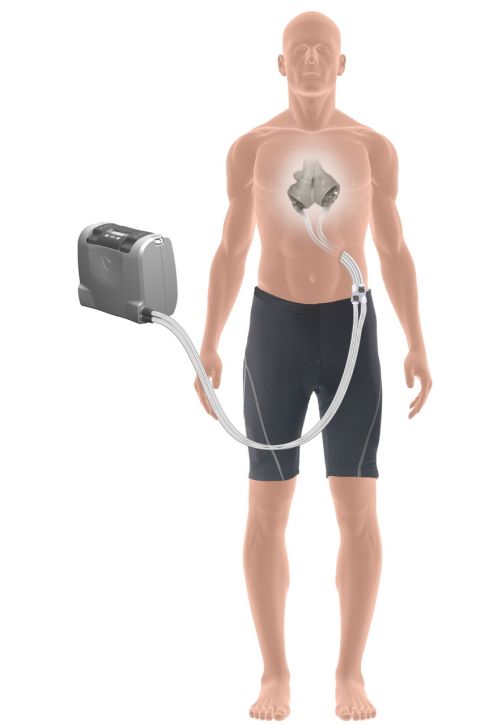

Schéma umelého srdca Zdroj: NÚSCH

Riadiacu jednotku si pacient nosí so sebou Zdroj: NÚSCH

Schéma umelého srdca Zdroj: NÚSCH

Riadiacu jednotku si pacient nosí so sebou Zdroj: NÚSCH